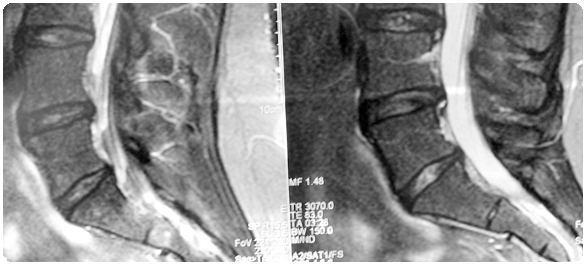

กระดูกเอว หรือกระดูกสันหลังเอว หรือกระดูกบั้นเอว (Lumbar spine หรือ Lumbar vertebrae) เป็นกระดูกสันหลังช่วงหลังตอนล่าง/ช่วงล่าง (Lower back) ที่อยู่ระหว่างกระดูกสันหลังอก (กระดูกสันหลังช่วงหลังตอนบน) โดยอยู่ต่อลงมาจากกระดูกสันหลังอกและต่ำจากกระดูกเอวลงมาคือ กระดูกใต้กระเบนเหน็บ โดยกระดูกเอวมีทั้งหมด 5 ข้อ ทางแพทย์มักเรียกย่อว่า L ( L1 ถึง L5, เป็นชื่อย่อจาก Lumbar)

กระดูกเอวเป็นกระดูกที่ช่วยรองรับน้ำหนักของร่างกาย และช่วยการเคลื่อนไหวร่างกายในเกือบทุกท่าทาง ซึ่งจะเป็นท่าทางที่ต้องแบกรับน้ำหนักและต้องทำซ้ำๆต่อเนื่อง ดังนั้นจึงเป็นสาเหตุให้พบโรคจากกระดูกส่วนนี้มากที่สุดเช่น โรคปวดหลัง (อ่านเพิ่มเติมได้ในเว็บ haamor. com มี 3 บทความดังนี้ ปวดหลัง, ปวดหลังช่วงล่าง และปวดหลังจากโรคหมอนรองกระดูกสันหลัง), โรคกระดูกสันหลังเสื่อม, โรคกระดูกสันหลังเอวเคลื่อน, โรคกระดูกพรุน, โรคกระดูกสันหลังหัก